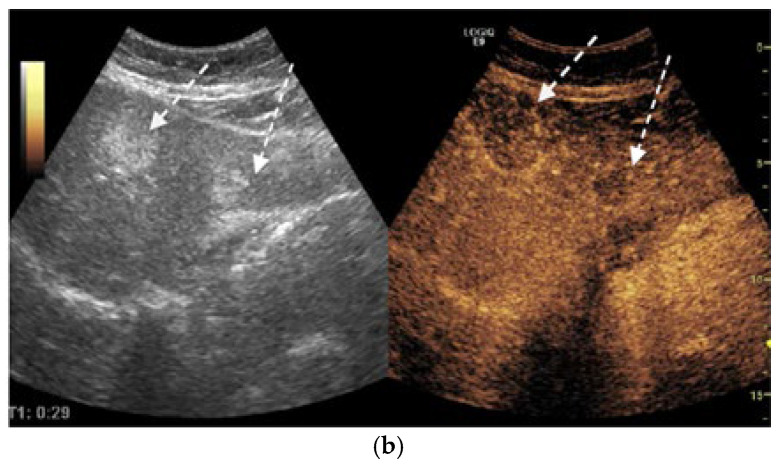

Background and Clinical Significance: Neuroendocrine neoplasms (NENs) are a group of malignancies that may remain clinically silent for many years. The presence of hepatic metastases can be the first clue leading to diagnosis. Case Presentation: We report the case of a 67-year-old man with intermittent tiredness and suspicious hepatic nodules detected on routine abdominal ultrasound. Contrast-enhanced ultrasonography showed arterial hyperenhancement with early washout, suggestive of metastases. Synchronous high-grade neuroendocrine carcinomas (NECs) of the lung and cecum were identified. Although the liver lesions were initially presumed to arise from the cecal tumor, liver biopsy immunohistochemistry was TTF-1 positive/CDX2 negative, whereas the cecal lesion was TTF-1 negative/CDX2 positive. This mutually exclusive immunophenotype confirmed two separate primary carcinomas. Given the high-grade histology, the patient received platinum-based chemotherapy and achieved a partial response. Conclusions: This case illustrates the diagnostic complexity of synchronous lesions and highlights the "mirage of the first lesion" phenomenon, in which the initially detected tumor may not represent the true primary site. A comprehensive, multidisciplinary strategy is crucial for establishing the correct diagnosis and guiding optimal management.